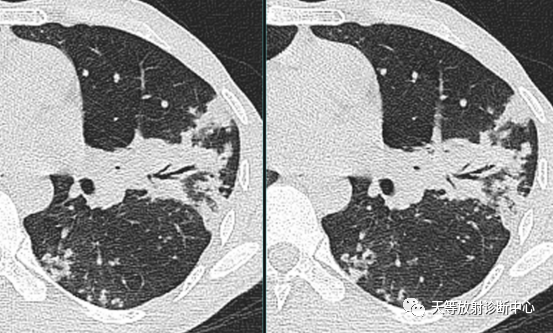

上图:左边病例:支原体肺炎,右侧肺炎,肺不张。

右边病例:两侧肺门影增大增浓。

病例来源:庄丽霞 张 芬.小儿肺炎支原体感染321例临床和影像学特点分析[J].福建医药杂志.2020.42(1):91-93.